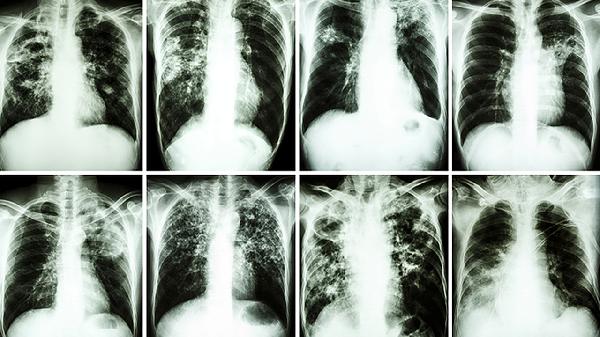

胸苷激酶是DNA合成关键酶,其活性升高提示细胞异常增殖。该指标对血液系统肿瘤、实体瘤早期筛查具有较高敏感性,尤其在白血病、淋巴瘤监测中价值显著。检测结果需结合影像学及其他肿瘤标志物综合判断。